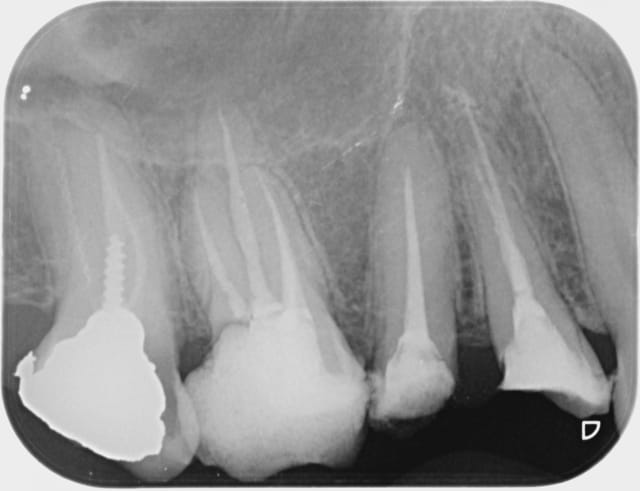

+1 l'interet c'est de faire partager ses astuces. Je ne prétend pas etre le roi de l'endo mais en ce qui me concerne j'ai trouvé une séquence qui me permet d'avoir des résultats reproductibles en un minimum de temps. Une autre 40 mn.

La plus simple lentulo scellement monocone, tuck back à l'apex quand même.

Bon , un cas clinique . Demain je mets la radio de l'endo de la 7 , mais voilà le lentulo sorti comme preuve de ma bonne fois . La 6 5 4 c'est moi . J'ai la moyenne ou je fais un procès à endo express ?